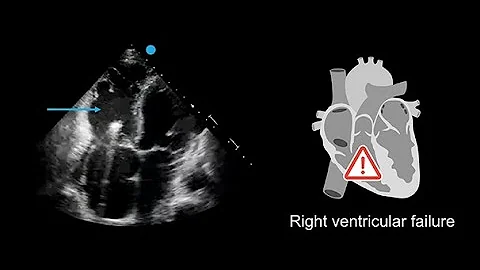

How To Assess Systolic Function With Echocardiography In Patients With Hcm

View our full Microlesson Series on HCM Playlist: bit.ly/3qixWyf In this video from ASE's Microlesson Series on Hypertrophic ...